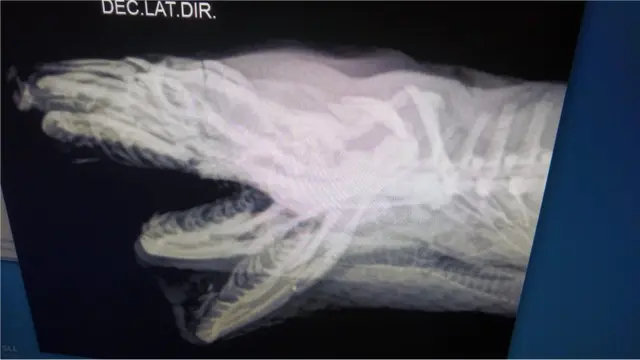

Uma jiboia de 2,4 metros que foi brutalmente agredida com pauladas na cabeça vem se recuperando com sucesso e virou símbolo contra a estigmatização das serpentes como animais perigosos.

'Santinha' foi encontrada pelo biólogo Izar Aximoff e por bombeiros em uma via pública perto do Parque Nacional da Tijuca, no Rio de Janeiro, e levada às pressas para o Instituto Vida Livre, uma ONG que atua na reabilitação e soltura de animais em situação de risco no Rio de Janeiro, onde recebeu cuidados médicos e continua a ser tratada.

Segundo o diretor do Vida Livre, Roched Seba, a serpente chegou com diversas fraturas e ferimentos na cabeça e em estado grave.

Ela foi medicada para reduzir sua dor extrema e os danos do ferimento, estabilizada e seguiu para uma rotina de exames radiograficos, para a posterior imobilização de sua mandíbula.

Durante os últimos três meses, Santinha passou por um longo processo de recuperação que incluiu uma série de cuidados, como medicação diária, limpeza da cavidade bucal, hidratação, alimentação forçada, aquecimento e exames constantes.

Ela também teve sua cabeça e mandíbula imobilizadas. Tratamentos alternativos que ajudam na cicatrização e reversão dos processos inflamatórios como o laser e a moxaterapia (técnica de acupuntura com calor), também foram usados.

Depois de três meses, a serpente agora está livre de sua imobilização bucal. Uma série de exames e acompanhamento clínico para analisar a cicatrização e o estado da lesão farão parte de sua rotina de reabilitação.